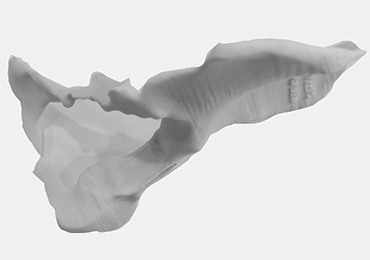

Step 1: The patient’s MRI film is converted into 3D.

Step 2: The bone model is printed.